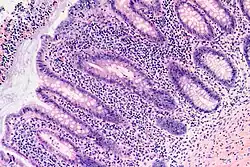

Die Appendizitis (lateinisch Appendicitis) oder Wurmfortsatzentzündung ist eine Entzündung des Wurmfortsatzes (Appendix vermiformis) am Ende des Blinddarms (des Caecums). Ist der Blinddarm entzündet, wird von einer Typhlitis gesprochen. Im Deutschen wird auch die Wurmfortsatzentzündung umgangssprachlich als Blinddarmentzündung bezeichnet. Die akute Appendizitis (Appendicitis acuta) stellt einen Notfall dar.

Der Wurmfortsatz (Appendix vermiformis), umgangssprachlich fälschlicherweise auch „Blinddarm“ genannt, ist ein Anhängsel am Blinddarm bei einigen Säugetieren. Beim Menschen ist er im Regelfall etwa zehn Zentimeter lang.

Als Ursache für die Appendizitis wird eine Abflussstörung des Appendixlumens in den Blinddarm vermutet. Daraus folgt eine Druckerhöhung im Wurmfortsatz, Minderperfusion der Darmwand und Einwanderung von Bakterien. Die Abflussstörung kann beispielsweise durch Abknickung, Narbenstränge, entzündliche Schleimhautschwellung oder Verlegung mit Kotsteinen oder Fremdkörpern verursacht werden.[1][2] Kotsteine, sogenannte Appendikolithe, können mit komplizierten Krankheitsverläufen assoziiert sein.[3] Im Gegensatz zu dieser Vermutung stehen andere Untersuchungen. Dabei wurden gelegentlich Kotsteine im Appendixlumen gefunden, ohne dass diese eine Entzündung verursachten.[4] Ein weiteres Beispiel sind Untersuchungen zur Druckerhöhung im Wurmfortsatz. Es wurden bei 19 von 33 Patienten mit Appendizitis keine Abflussstörung des Appendixlumes festgestellt. Die tatsächliche Ursache wird in wesentlich komplexeren Zusammenhängen vermutet.[5]